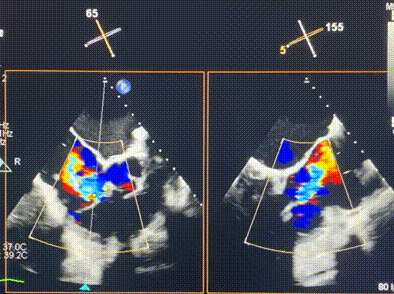

術(shù)前超聲提示重度三尖瓣反流

接受本次LuX-Valve Plus治療的是一位三尖瓣重度反流的高齡女性,患者早前曾由于二尖瓣疾病行經(jīng)導(dǎo)管二尖瓣置換術(shù),植入Tendyne瓣膜一枚,且有ICD植入史。術(shù)前CT分析結(jié)果顯示,瓣環(huán)大小為47.6mm,血管無明顯迂曲和鈣化。由于患者三尖瓣解剖結(jié)構(gòu)復(fù)雜,二尖瓣位人工瓣膜造成的超聲偽影和ICD導(dǎo)線的干擾使得歐洲沒有其他合適的商業(yè)化和臨床試驗的產(chǎn)品可以對其進行治療。經(jīng)過Rodrigo Estévez-Loureiro教授團隊的詳盡術(shù)前評估,認為LuX-Valve Plus經(jīng)導(dǎo)管三尖瓣置換系統(tǒng)可以對該患者進行有效的治療。因此,Rodrigo Estévez-Loureiro教授團隊最終決定使用這一中國創(chuàng)新器械為患者進行手術(shù)。法國波爾多里爾大學(xué)附屬醫(yī)院的Thomas Modine教授與加拿大圣保羅醫(yī)院的Anson Cheung教授全程線下指導(dǎo)本次手術(shù)。